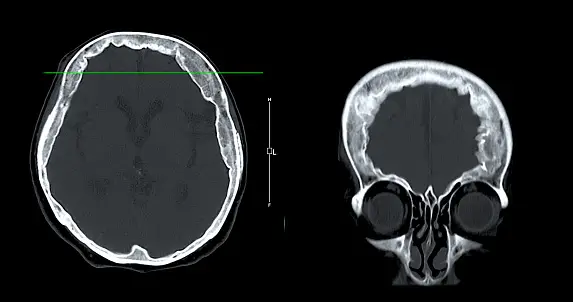

- 컴퓨터 단층촬영(CT): CT는 뇌의 단면 영상을 생성하여 뼈와 같은 뇌 구조의 이상을 확인하는 데 사용됩니다. 종양을 강조하기 위해 대비제를 사용할 수도 있습니다.